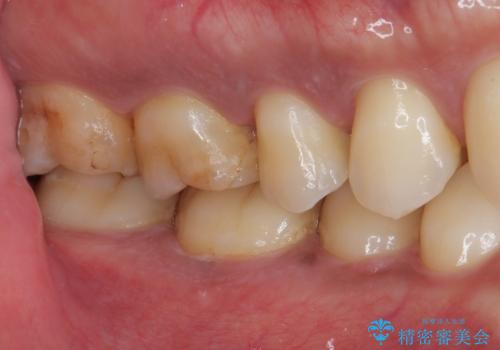

前から6番目の歯の頬側は個人差はありますが笑った時に見えるのでセラミックによる治療を行うと非常に審美的です。

見た目、機能面ともに満足していただけました。

噛み合わせが強いので今後はナイトガードを使ってもらいながらメンテナンスで通ってもらい経過を診ていく予定です。